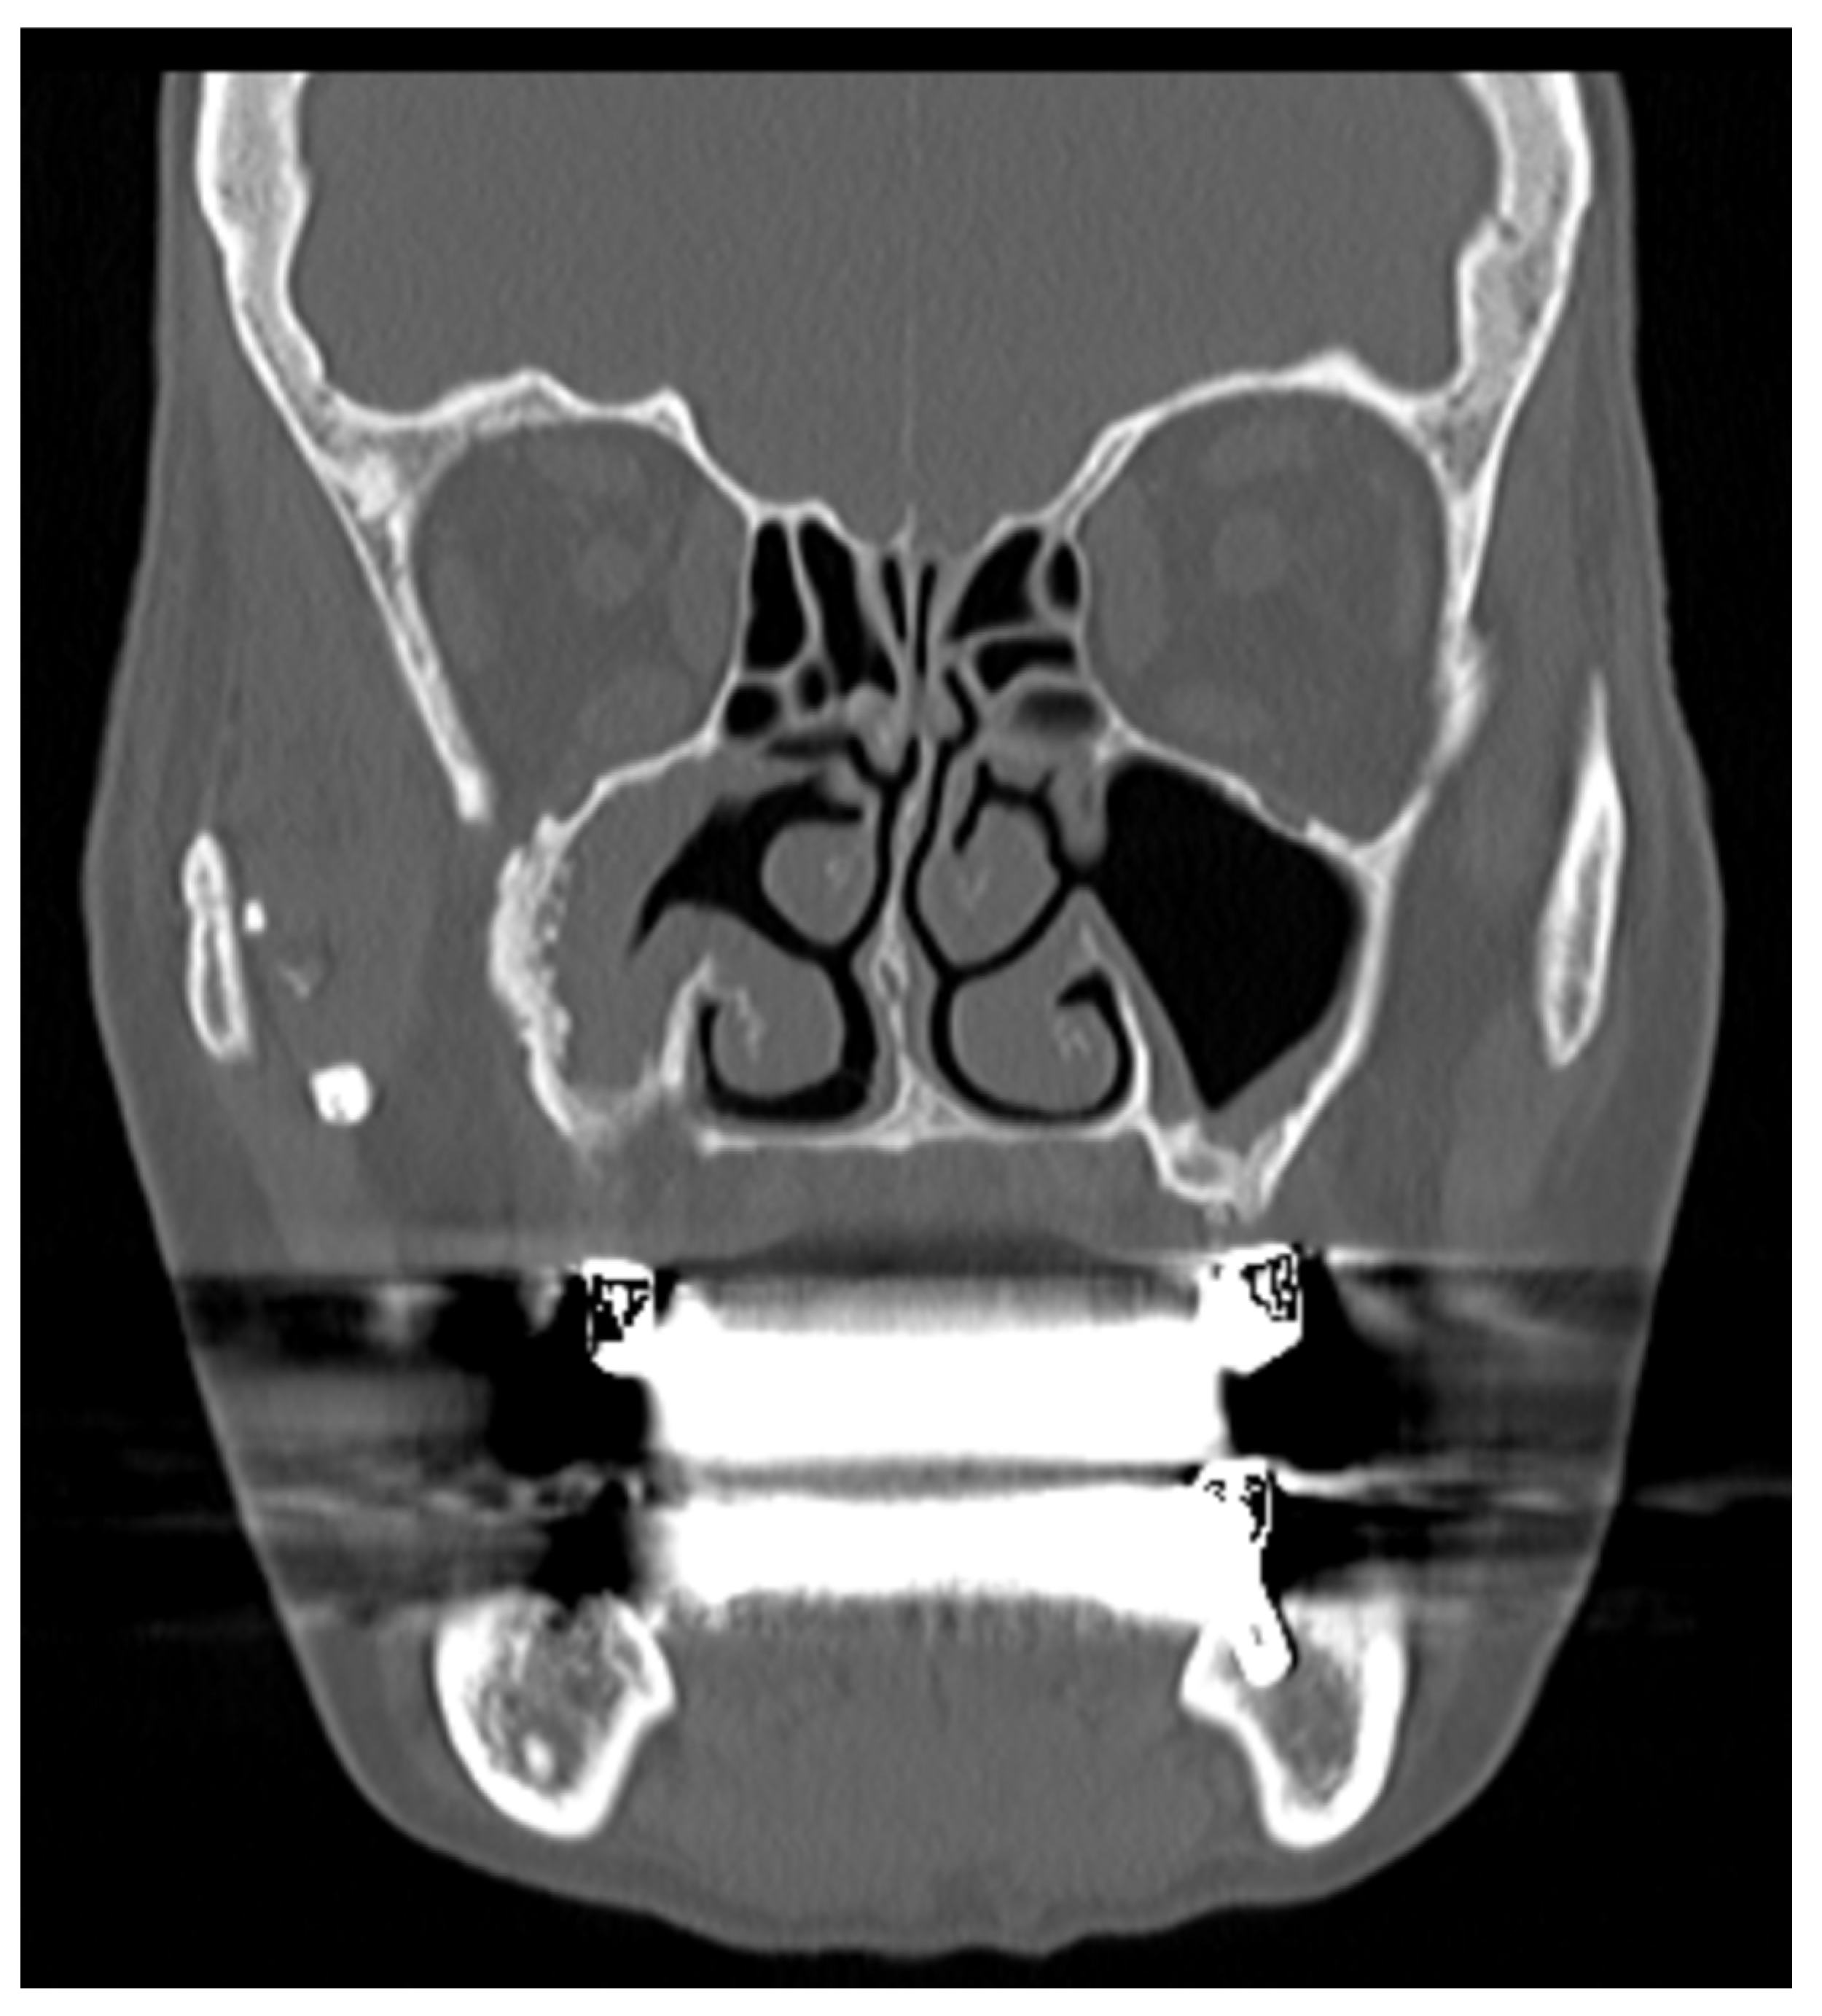

• A patient presenting sinusitis symptoms for more than 4 months, after an implantological treatment, without a foreign body in the maxillary sinus, without obstruction of the OMC and with OAF, can be identified as: TaEaB0O1F1 [Figure 3]

Figure 3. Slice TC of patient with TaEaB0O1F1.